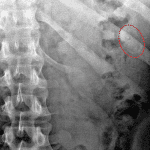

- Faint oval radiopaque density overlying the left hemiabdomen

- Ingested foreign body (aluminum soda can tab)

Faint oval radiopaque density overlying the left hemiabdomen concerning for ingested foreign body given the history. This may be in the proximal small bowel, although location cannot be confidently confirmed on these radiographs.